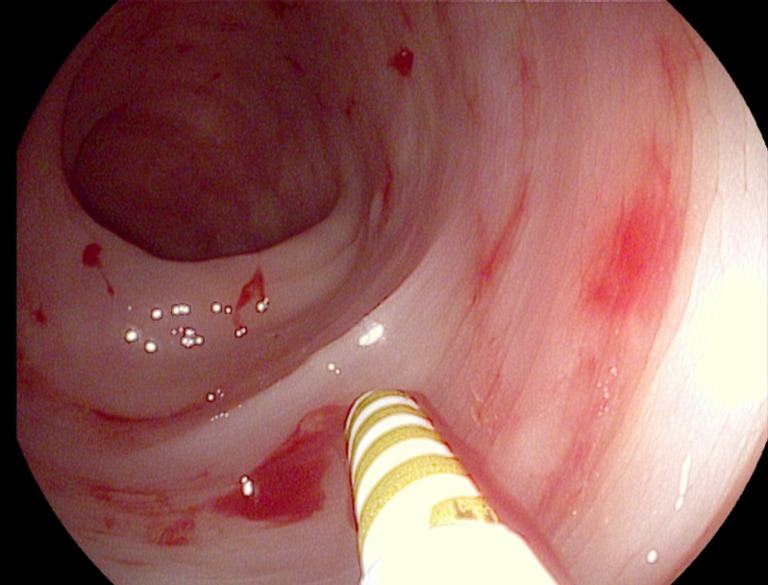

2. Viêm loét dạ dày tá tràng

Viêm loét dạ dày căn bệnh dạ dày gây tổn thương viêm và loét trên niêm mạc dạ dày hoặc tá tràng (phần đầu của ruột non), tổn thương xảy ra khi lớp niêm mạc của dạ dày hay tá tràng bị bào mòn và các lớp bên dưới thành dạ dày hay thành ruột sẽ bị lộ ra. Vết loét ở tá tràng chiếm 95%, vết loét ở dạ dày chiếm 60%, trong đó vết loét ở bờ cong nhỏ dạ dày chiếm 25% các trường hợp.

3. Xuất huyết dạ dày (chảy máu dạ dày)

Xuất huyết dạ dày là một kiểu biến chứng của bệnh viêm loét dạ dày trong thời gian dài không được khắc phục và điều trị. Đây là căn bệnh gây nguy hiểm đến tính mạng khi mất máu quá nhiều.

6. Nhiễm vi khuẩn Hp dạ dày

Vi khuẩn HP có tên gọi đầy đủ là Helicobacter pylori. Theo thống kê có tới 70% người Việt nhiễm vi khuẩn HP. Vi khuẩn HP là nguyên nhân chính dẫn đến các bệnh dạ dày khác như viêm loét dạ dày, tá tràng đặc biệt là ung thư dạ dày.

- Thông thường, vi khuẩn Helicobacter pylori (HP) thường gặp phải ở lớp màng nhầy của dạ dày, tá tràng và có thể yên vị ở trong đó. Tuy nhiên, khi gặp phải môi trường thuận lợi như độ pH trong dạ dày mất ổn định, sức đề kháng của cơ thể yếu đi thì chúng sẽ phá vỡ lớp nhầy để tấn công vào niêm mạc dạ dày và gây tổn thương.

BSCKII. Lê Kim Sang đã có hơn 30 năm kinh nghiệm điều trị trong lĩnh vực nội soi và nội tiêu hóa.

TS.BS. Hứa Thúy Vi đã có hơn 14 năm kinh nghiệm khám và chữa bệnh Nội tiêu hóa – gan mật và Nội soi tiêu hóa.